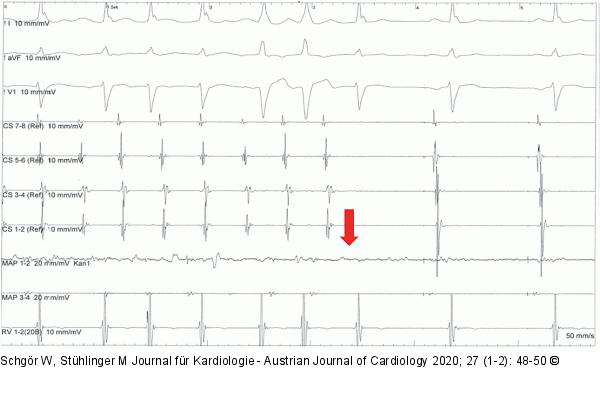

Abbildung 3: Elektroanatomisches Mapping Elektrophysiologisches Mapping der Tachykardie mit Terminierung während der ersten Radiofrequenz-Ablation: Die Aktivierung im Kororonarsinus läuft von proximal (CS 7/8) nach distal (CS 1/2), hinweisend für einen rechtsatrialen Ursprung. Im Bereich des Ablationskatheters (MAP) ist ein fraktioniertes, mitt-diastolisches Potential sichtbar. Der rote Pfeil zeigt den Zeitpunkt der Terminierung der Tachykardie (6 Sek. nach Beginn der Ablation). |

Elektrophysiologisches Mapping der Tachykardie mit Terminierung während der ersten Radiofrequenz-Ablation: Die Aktivierung im Kororonarsinus läuft von proximal (CS 7/8) nach distal (CS 1/2), hinweisend für einen rechtsatrialen Ursprung. Im Bereich des Ablationskatheters (MAP) ist ein fraktioniertes, mitt-diastolisches Potential sichtbar. Der rote Pfeil zeigt den Zeitpunkt der Terminierung der Tachykardie (6 Sek. nach Beginn der Ablation). |